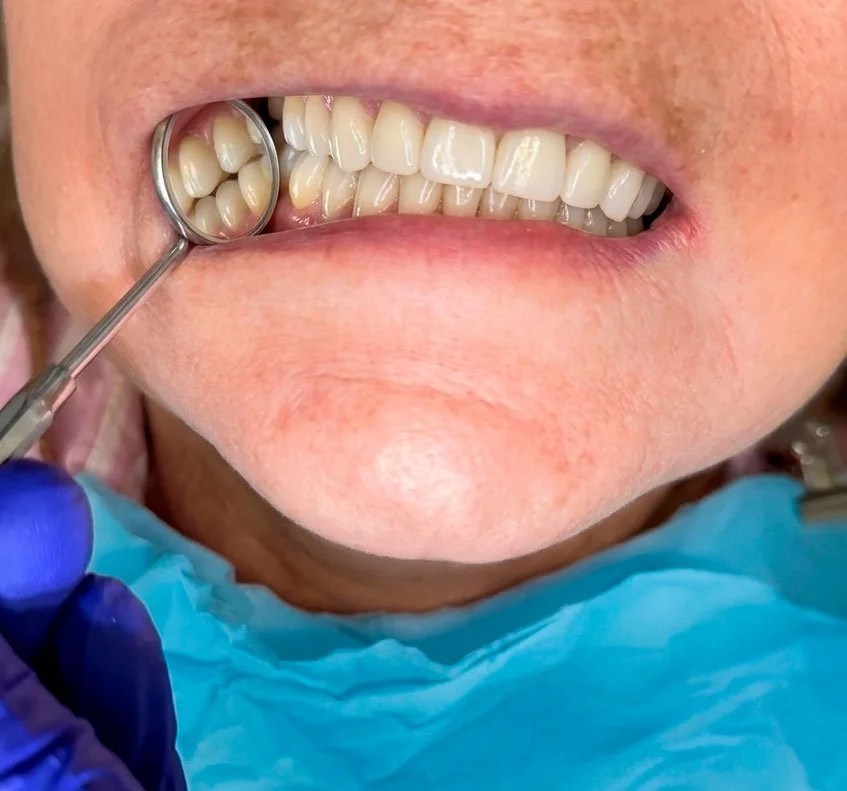

Quinto paso: Ajustes oclusales

En la etapa final probamos la rehabilitación en boca y realizamos los ajustes necesarios para lograr una mordida equilibrada y cómoda. Se revisa la oclusión, se pulen los detalles finales y el paciente queda listo para disfrutar de su nueva sonrisa con controles periódicos.